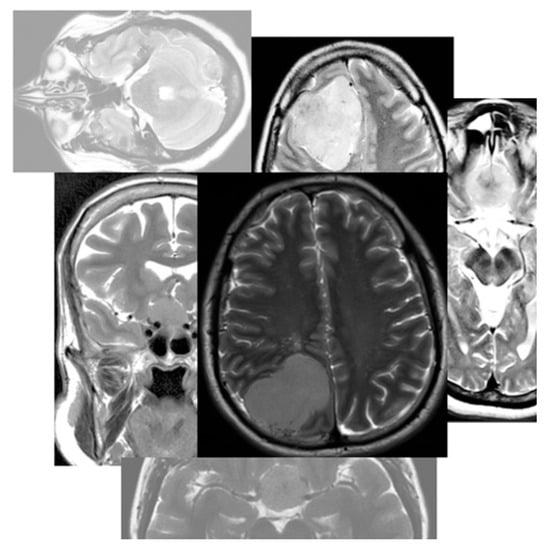

The research experiments utilized a genuine dataset of brain tumor images generously provided by King Khalid University Hospital (KKUH) in Riyadh, Saudi Arabia [4]. This dataset comprises 28 cases involving both female and male subjects diagnosed with meningioma tumors. Out of these cases, 19 are identified as having firm tumors, while the remaining cases exhibit soft tumors. The dataset was meticulously labeled by a skilled surgeon, who leveraged their diagnostic expertise to categorize each case as either firm or soft. In total, the collected dataset encompasses 500 MRI images, which were subsequently partitioned into a training set (70% of images) and a testing set (30% of images). The training set, containing 350 MRI images, demonstrates a class distribution of 32% for soft meningioma and 68% for firm meningioma. Similarly, the testing set comprises 150 MRI images, with 32% representing soft meningioma tumors and the remaining 68% corresponding to firm cases. The two defined classes are as follows: soft tumor (class 1) and firm tumor (class 0). All images in the dataset are accompanied by .txt file labels, and the image-labeling process utilized the labelImg tool. Each object within an image is labeled in the following format:

The image-cropping procedure was executed manually by a qualified radiologist. This process is initiated by selecting a region of interest (ROI) covering the entire area of the brain tumor from the MRI images. The radiologist drew a rectangle box around the largest tumor area, which varied in size across cases. Subsequently, the tumor type was classified by the radiologist, as illustrated in Figure 11. This manual cropping step aimed to facilitate the training of all employed YOLO models. The experiments were conducted on Google Colaboratory, also known as “Colab”. It is an online tool by Google Corporation utilized for data analysis, machine learning, and education. The hardware accelerator employed was a NVIDIA Tesla T4 GPU, which is manufactured by NVIDIA Corporation. NVIDIA’s headquarters are located in Santa Clara, California, United States. with 40 cores, a clock rate of 1.59 GHz, and a random-access memory (RAM) of 16 GB [36].